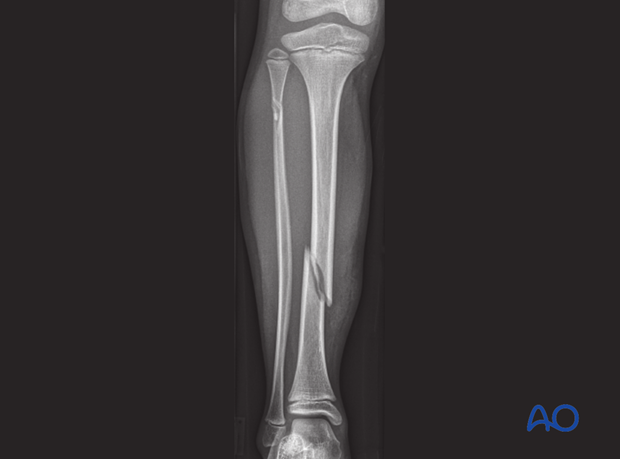

Oblique fracture - Definition

The fracture occurs sloped up or down at an angle or curves

Oblique fracture - Cause

Trapping of one bone while the other twists over it

Ex. Foot caught in a rock and the leg twists

Oblique fracture